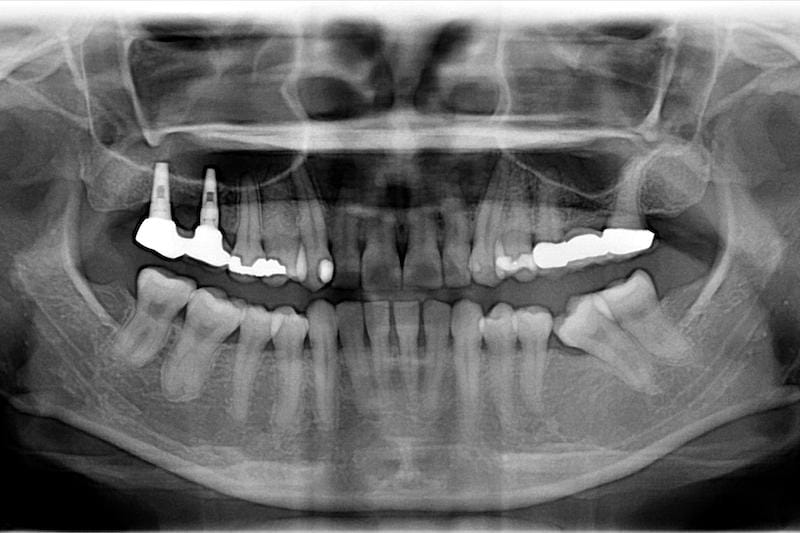

真實案例 首頁 真實案例 一日全瓷貼片 大谷主水.夢多Dr.任杏嫦 吃美食前要先有一口好牙才能安心品嘗,所以夢多來到了楊梅在地鄉民都激推的當代牙醫做數位一日全瓷貼片,懷 ... MORE 一日全瓷貼片 樂天女孩琳妲Dr.任杏嫦 琳妲以前有做過矯正,但是後來門牙又慢慢突出來,而且晚上睡覺有磨牙,門牙就被磨得短短的。全瓷貼片不僅可 ... MORE 嚴重牙周病治療: 療程含慢性牙周病/植牙補骨/人工植牙/全瓷冠Dr.葉立維 Mr. Wang 是一位工程師,因為上顎前面的舊假牙有不美觀以及密合度比較差的問題,其他醫師先幫他拆除舊假 ... MORE 中度牙周病治療: 全口牙周病/牙冠增長術/鼻竇增高術Dr.葉立維 Miss Feng也是很怕看牙,因此即使自己知道牙齒有問題,也會一直拖延到沒辦法忍耐才會看醫生。2015年我幫 ... MORE 牙周病治療:牙齦萎縮治療/輕微牙周病/全瓷冠Dr.葉立維 門診時除了牙周病患者之外,也很常遇到患者覺得牙齒酸痛而來檢查,造成牙齒酸痛的原因除了蛀牙外,很常見到 ... MORE 輕微牙周病治療 全口牙周病/游離牙齦移植術Dr.葉立維 第一次幫 Miss Sung 評估時,她主要想處理的位置是在左下後牙區,我們可以看到她有兩顆假牙,另外更後面 ... MORE 牙周病治療推薦: 全口牙周病/全瓷冠假牙/陶瓷貼片/植牙Dr.葉立維 Mrs.Hsieh是我在十多年前治療過的全口牙周病和植牙患者。她最近因爲右下的假牙搖晃,牙齦發炎流血,咬合 ... MORE 舒眠植牙治療推薦: 根管治療後植牙/陶瓷貼片療程Dr.葉立維 Mr.Su是從南台灣到桃園求學,學業完成後在科技業工作。在求學過程中因為課業繁忙,沒有不舒服也不曾想到應 ... MORE 中度全口牙周病治療,牙周美學手術/陶瓷貼片Dr.葉立維 牙周病因為初期或中期都不太會引起劇烈疼痛,很多人是定期洗牙或檢查時才被醫師發現。有時甚至局部有嚴重牙 ... MORE 牙冠增長術改善笑齦,全瓷貼片打造「完美微笑曲線」Dr.葉立維 Miss Wu接受全口齒顎矯正治療完成。雖然牙齒已經排列整齊,但牙齒外觀似乎和『美』還有一段差距。 MORE 全口牙周病治療,牙周美學手術恢復美觀自信Dr.葉立維 Mr.Lin最初因為左邊下面臼齒牙齦腫脹前來檢查,通常遇到這樣情況,確實很多人會懷疑自己是不是得了牙周病 ... MORE 植牙案例宋先生 / Dr.程昱嘉 我是因為嚴重的牙周病,造成牙齒鬆動,需要進行牙周病治療及後續的8顆植牙。一開始到楊新診所就體驗到較先 ... MORE 一般牙科楊小姐 / Dr.葉立維 因為之前補的牙掉落,導致無法正常吃東西影響美觀,所以來當代楊新牙醫診所,給葉立維醫師看過後,才明白我 ... MORE 植牙案例覃小姐 / Dr.梁嘉元 首先~謝謝梁嘉元&漂亮的助理,我是一個很愛笑的人,因為智齒、蛀牙去了當代牙醫植牙中心,評估下要植 ... MORE 植牙案例戴小姐 / Dr.梁嘉元 梁嘉元醫師非常細心和耐心,治療期間讓非常害怕看牙醫的我很安心,經歷近三年的長期植牙過程,感受到梁醫師 ... MORE 植牙案例蘇小姐 / Dr.梁嘉元 從小到大最怕就是看牙,第一次覺得看牙齒ㄧ點都不可怕,梁醫生很細心溫柔,每次用牙齒我都快處於睡眠狀態, ... MORE 全口重建陳先生 / Dr.梁嘉元 當天拔牙,當天植牙手術完就有牙,不會醜醜的沒有門面,真是太好了! MORE 全口重建葉先生 / Dr.梁嘉元 本人因多年前工作需要,必須台灣-大陸兩地往來,因此在牙齒的治療上延誤! 因為當年大陸醫學及醫療環境不 ... MORE 植牙案例林小姐 / Dr.梁嘉元 一走進當代牙醫,感受到的是精心打造溫馨雅致的環境及舒適的空間,使我能以愉悅的心情下接受治療。 剛開始 ... MORE 全口重建廖先生 / Dr.梁嘉元 牙齒的問題在我的人生中一直是一個不想面對,但又擺脫不了噩夢。 MORE 全口重建梁先生 / Dr.梁嘉元 在進行 A l l o n 4 一日全口重建前心裡的壓力還蠻大的,但是手術結束後卻沒有什麼感覺,而且手術和結果 ... MORE «12»